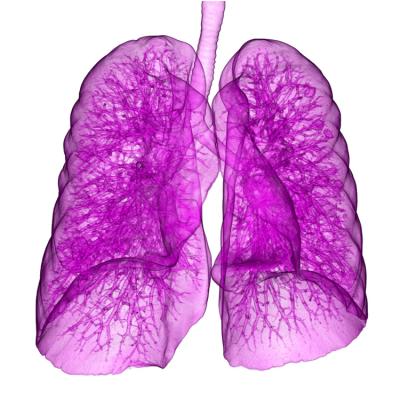

January 22, 2015 — Patients who received post-operative radiation therapy (PORT) lived an average of four months longer when compared to patients who had the same disease site, tumor histology and treatment criteria but did not receive PORT, according to research presented at the 2014 Chicago Multidisciplinary Symposium in Thoracic Oncology. The symposium is sponsored by the American Society of Clinical Oncology (ASCO), the American Society for Radiation Oncology (ASTRO), the International Association for the Study of Lung Cancer (IASLC) and The University of Chicago Medicine.

This study reviewed the records of non-small cell lung cancer patients treated from 2004 to 2006 from the National Cancer Data Base (NCDB), a joint endeavor of the Commission on Cancer of the American College of Surgeons and the American Cancer Society. The study authors acquired the data for patients who had surgically resected non-small lung cancer with pathologically involved N2 (pN2) lymph nodes (tumors had spread to the lymph nodes in the center of the chest) and who received chemotherapy. The database was further queried to exclude patients with positive margins, incomplete survival data, those who did not receive adjuvant chemotherapy, histology other than NSCLC, and patients treated with Cobalt-60, non-beam radiotherapy or neoadjuvant radiotherapy. Two thousand one hundred and fifteen patients (2,115) met all of the study criteria. Forty-three percent of patients (918) received PORT; 56.6 percent of the patients (1,197) were not treated with PORT.

Factors associated with overall survival (OS) were assessed through a multivariable Cox proportional hazards model. Inverse probability of treatment weighting (IPTW) using the propensity score was also implemented to reduce biased treatment selection. Using an adjusted Kaplan-Meier estimator and the weighted log-rank test based on the IPTW, patients treated with PORT had an improved overall survival (median survival time) of 42 months compared to 38 months for the patients not treated with PORT (p=0.048).

Multivariable analysis revealed that female gender, adenocarcinoma histology, higher income, urban/rural setting vs. metropolitan setting, lower T state, 1-2 involved lymph nodes vs. =3 examined and involved lymph nodes, and younger age correlated to better OS (p<0.05). No direct relation was found between the effects of PORT and the number of involved lymph nodes.

“These results reinforce the value of PORT for non-small cell lung cancer patients with involved mediastinal lymph nodes. Our data indicates that with modern radiotherapy equipment and treatment techniques, PORT can improve survival for these patients,” said John L. Mikell, MD, lead study author and chief resident in the Department of Radiation Oncology at Emory University Winship Cancer Institute in Atlanta. “The data in this study, the largest, most recent cohort of patients with involved mediastinal nodes treated with chemotherapy reinforce that PORT should be considered in addition to chemotherapy following resection of non-small cell lung cancer.”